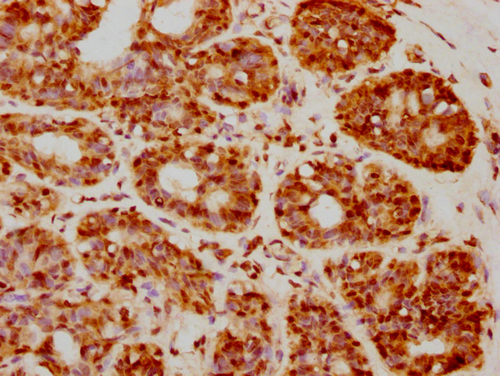

IHC image of CSB-PA010403PA05nforHU diluted at 1:20 and staining in paraffin-embedded human breast cancer performed on a Leica BondTM system. After dewaxing and hydration, antigen retrieval was mediated by high pressure in a citrate buffer (pH 6.0). Section was blocked with 10% normal goat serum 30min at RT. Then primary antibody (1% BSA) was incubated at 4°C overnight. The primary is detected by a biotinylated secondary antibody and visualized using an HRP conjugated SP system.